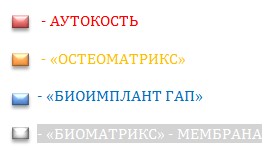

Мембрана Биоматрикс (Рис.13)  Применение коллагеновой мембраны препятствует миграции частиц материала за пределы операционной зоны и обеспечивает надёжную изоляцию на длительный период (1-2 месяца) послойного кластера от слизистой, что необходимо для ... (более подробно читайте «БИОМАТРИКС» - МЕМБРАНА). Послойный вид используемых материалов:

Применение коллагеновой мембраны препятствует миграции частиц материала за пределы операционной зоны и обеспечивает надёжную изоляцию на длительный период (1-2 месяца) послойного кластера от слизистой, что необходимо для ... (более подробно читайте «БИОМАТРИКС» - МЕМБРАНА). Послойный вид используемых материалов: